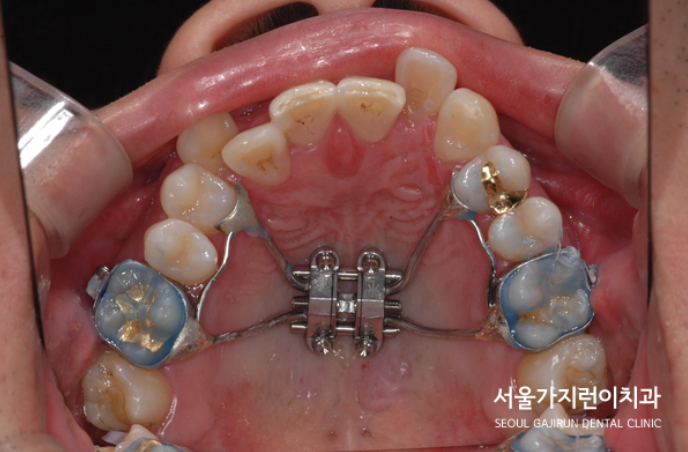

여기에 치아 상실로 비어버린 공간도 있는 케이스였는데요. 따라서 아래 하악 양쪽 치아가 쓰러져 있었는데요. 씹는 면이 기울어져 있었기 때문에 음식을 씹는 것도 쉽지 않았습니다. 이런 상태를 비수술로 치아교정을 진행해보게 되었는데요. 교정을 통해 적절한 공간을 만들어 임플란트를 식립하게 되었습니다. 환자분의 경우 MARPE 상악골 확장장치를 사용해 교정을 진행하게 되었는데요. 하악에 비해 상악골이 좁았기 때문에 위턱의 공간을 확보하면서 교정을 시작하게 되었습니다.

전치의 교차교합과 턱뼈의 비대칭, 주걱턱의 개선을 위해 잇몸뼈에 미니스크류를 식립한 것도 사진으로 남겼습니다. 치아교정 과정은 이런 식으로 진행이 되었으며 교정치료를 시작한 지 33개월 만에 장치를 제거하게 되었는데요. 긴 교정기간이었지만 환자의 입장에서 비수술로 치아교정을 마칠 수 있게 되어 만족도가 높았던 케이스였습니다.